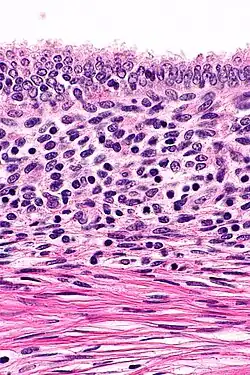

On microscopic examination, patterns of smooth muscle and endometrial tissue must be assessed with care to differentiate adenomyomas from masses of similar appearances, such as endometriosis containing smooth muscle and leiomyomas containing endometriosis.[3]